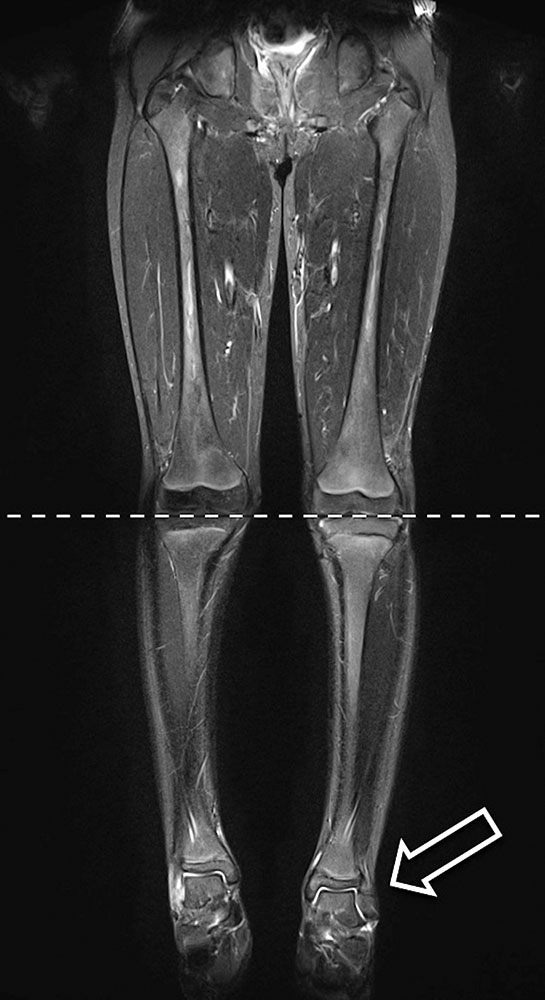

Young patient with PTEN hamartoma syndrome and progressive arteriovenous malformation in PTEN hamartoma at the knee; embolization therapy

Child with Parkes-Weber syndrome of the leg; clinical course and embolization